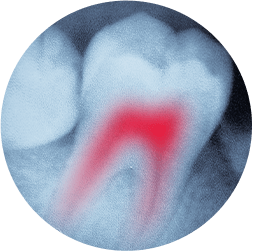

root canal therapy

If you develop an infection in one of your teeth you can experience pain and swelling and could even risk losing the tooth. Dr. Michel Raad and his team offer root canal therapy to relieve your discomfort and restore the health of your tooth. We will do everything we can to keep you comfortable and explain your aftercare needs.